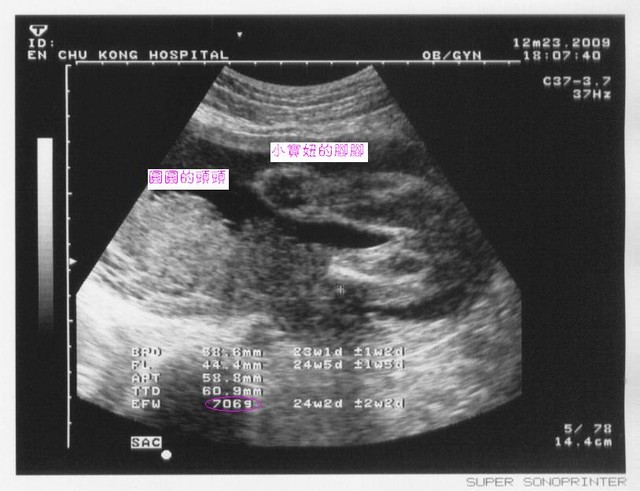

|

2010.01.18高層次超音波 |

2010.01.20例行產檢 |

週數 |

28週又3天 |

28週又5天 |

頭骨橫徑 |

7公分 |

7.43公分 |

大腿骨橫徑 |

5.16公分 |

5.01公分 |

預估體重 |

1178公克 |

1124公克 |